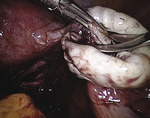

Uchwycono grasperem brzeg fenestracji jajnika. Nożyczkami wycięto 5-milimetrowy fragment brzegu torbieli – połączenia torbieli z niezmienioną tkanką jajnika (ryc. 4). Uwidoczniono granicę między niezmienionym jajnikiem a torebką torbieli (ryc. 5). Delikatnie pociągając torebkę jajnika, jednocześnie drugim narzędziem przytrzymując jajnik, przy pełnej wizualizacji oddzielanej granicy, całkowicie wyłuszczono torbiel. Podczas tego manewru większe krwawienie kontrolowano na bieżąco za pomocą kleszczyków bipolarnych (punktowo, „na sucho” z pomocą rurki ssąco-płuczącej (ryc. 6). Jajnik zszyto szwem zetkowym. Analogicznie po stronie prawej wsunięto pod prawy jajnik narzędzie wprowadzone przez prawy trokar. Podczas uwalniania zrostów jajnika z otrzewną dołka jajnikowego doszło do fenestracji torbieli i wylała się treść o barwie czekoladowej. Wycięto fragment brzegu torbieli (ryc. 7) i po uwidocznieniu granicy (ryc. 8) wyłuszczono w całości torbiel. Jajnik zeszyto szwem zetkowym. Wyłuszczone torbiele wyjęto na zewnątrz w endobagu.